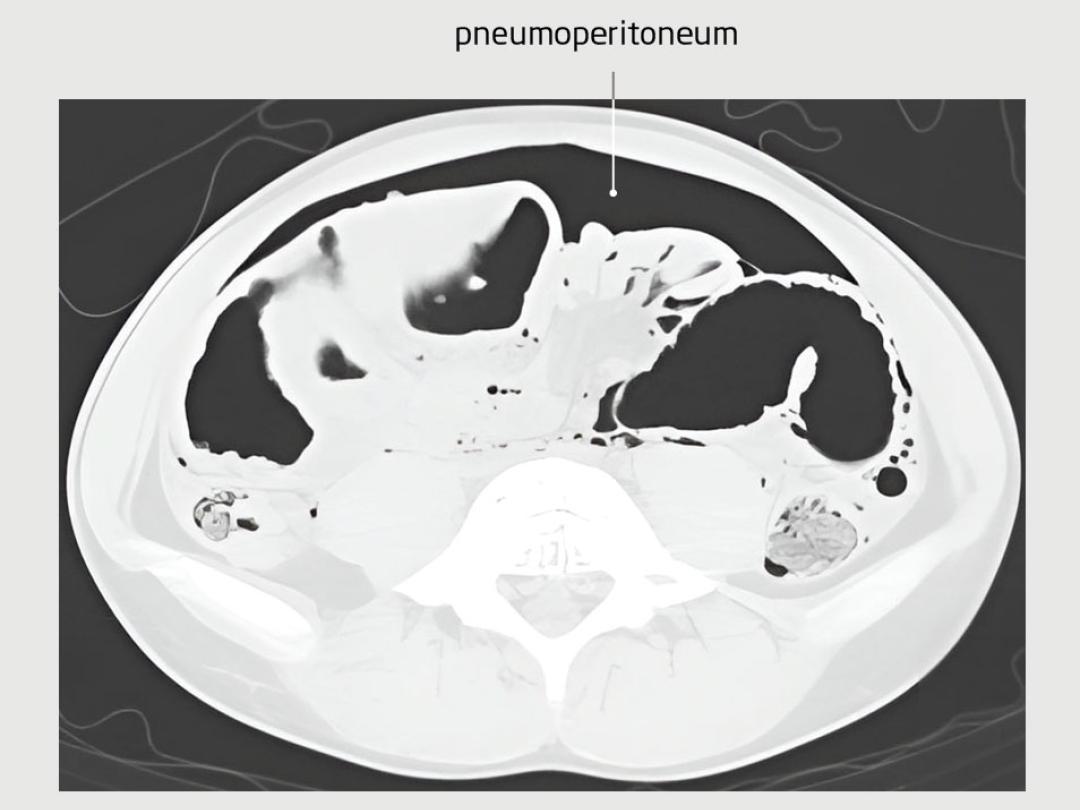

Post-mortem-CT-scan

Een 12-jarige jongen kwam bij de huisarts vanwege aanhoudende buikpijnklachten en hevig braken. Hij collabeerde in de huisartsenpraktijk en werd gereanimeerd tijdens het vervoer naar het ziekenhuis. Daar aangekomen overleed hij. Zijn voorgeschiedenis vermeldde een pyloromyotomie via een supra-umbilicale incisie. Het postoperatieve beloop werd gecompliceerd door een fasciedehiscentie, waarvoor een hersteloperatie werd verricht. Sinds zijn zesde levensjaar had de patiënt recidiverende buikpijnklachten gehad. Bij obductie werd feces gezien in de vrije buikholte en een tweetal darmperforaties bij een adhesie van het jejunum aan de buikwand ter hoogte van het litteken van de pyloromyotomie. Distaal van de adhesie was sprake van een inwendige herniatie van het dunnedarmpakket.